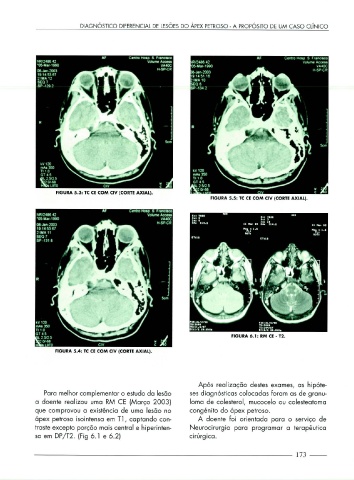

FIGURA 5.3: TC CE COM CIV (CORTE AXIAL).

FIGURA 5.5: TC CE COM CIV (CORTE AXIAL).

FIGURA 6.1: RM CE - T2.

FIGURA 5.4: TC CE COM CIV (CORTE AXIAL).

Para melhor complementar o estudo da lesão ses diagnósticos colocadas foram as de granu-

a doente realizou uma RM CE (Março 2003) loma de colesterol, mucocelo ou colesteatoma

que comprovou a existência de uma lesão no congénito do ápex petroso.

ápex petroso isointensa em Tl , captando con- A doente foi orientada para o serviço de

traste excepto porção mais central e hiperinten- N eurocirurgia para programar a terapêutica

sa em DP / T2. (Fig 6 . 1 e 6 .2) cirúrg ica.